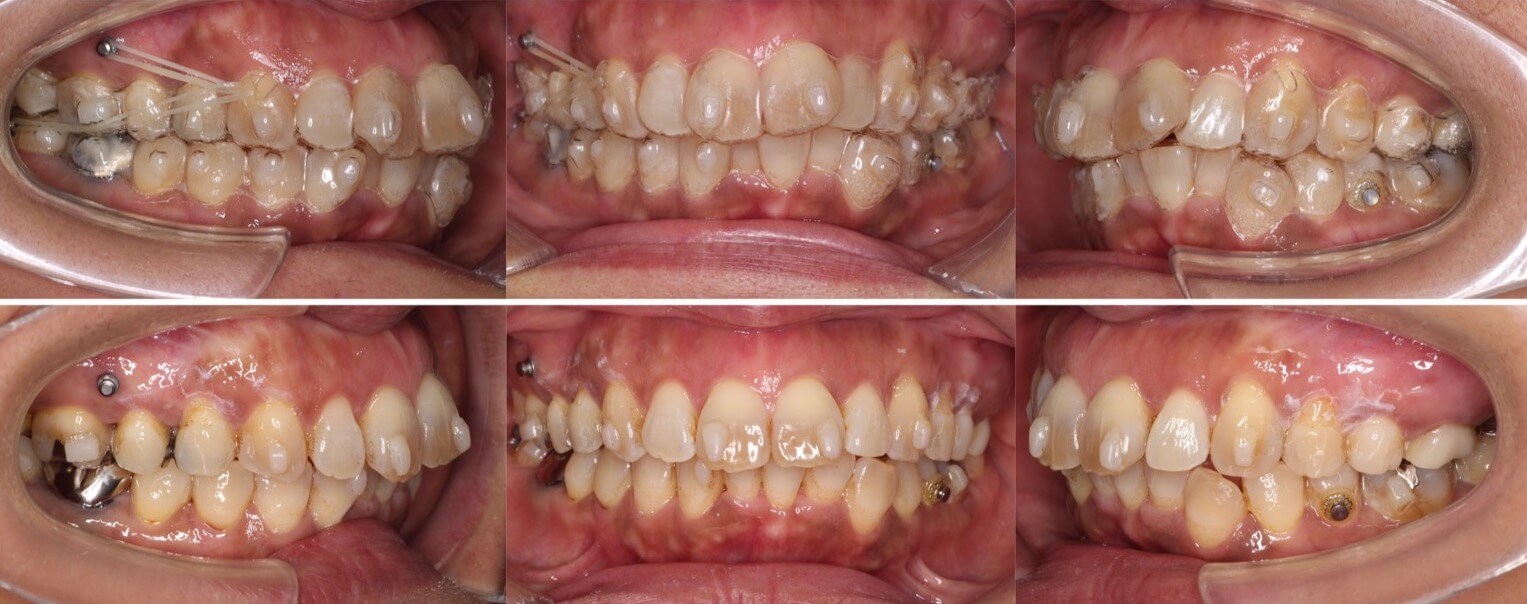

42歳女性・重度叢生・マウスピース装置

ミドルエイジの矯正治療では、できる限り抜歯を併用しないのですが、このように重度のがたつきがある場合は、抜歯を併用します。

<症例概要>

主訴:がたつき

年齢・性別:40代女性

住まい:千葉県佐倉市

症状:叢生・下顎右辺・右II級

抜歯:上左右4番・左下4番(計3本)

治療方針:抜歯空隙閉鎖

治療装置:マウスピース型矯正装置(アライナー装置)

治療期間:2年0か月

アライナー枚数:34+27-14ステージ

リテーナー:上フィックスタイプ+プレートタイプ

治療費用:990,000(税込)

代表的副作用:痛み・治療後の後戻り・歯根吸収・歯髄壊死・歯肉退縮

▶︎その他の副作用

【治療シミュレーション】

上の抜歯空隙に、ゆっくりと確実に犬歯を移動させます。